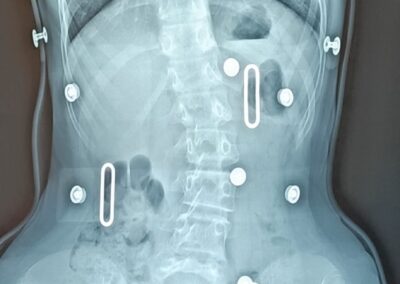

Corsets anti-scoliose

La scoliose est une déviation de la colonne vertébrale dans les 3 plans de l’espace. Celle-ci amène une silhouette asymétrique (visible au niveau des épaules et de la taille) et l’apparition de gibbosités (bosse), ainsi qu’un déséquilibre et une limitation de mouvement du tronc. Dans certains cas graves, la capacité respiratoire du patient peut se trouver limitée.

La scoliose est une pathologie qui se développe souvent pendant l’enfance et évolue progressivement au fil de la croissance. L’évolution est généralement lente dans période prépubère puis connait une accélération au moment de la puberté. Un examen médical est le seul moyen de détecter cette pathologie, les patients atteints ne souffrant en général pas de douleurs dorsales.

Le traitement se fait par appareillage au moyen d’un corset orthopédique sur mesure, moulé sur le corps et conçu de manière à permettre une croissance normale du rachis en corrigeant les déformations existantes.

Chaque corset est réalisé et adapté selon la morphologie du patient. Il tient compte de la déformation du rachis, du poids et de la taille de celui-ci, ainsi que de la prescription médicale. Selon la déformation du rachis et le modèle de corset prescrit, les temps de port de ce dernier peuvent être variables. De même des ajustements peuvent être réalisés selon l’évolution de la pathologie et de la morphologie du patient.